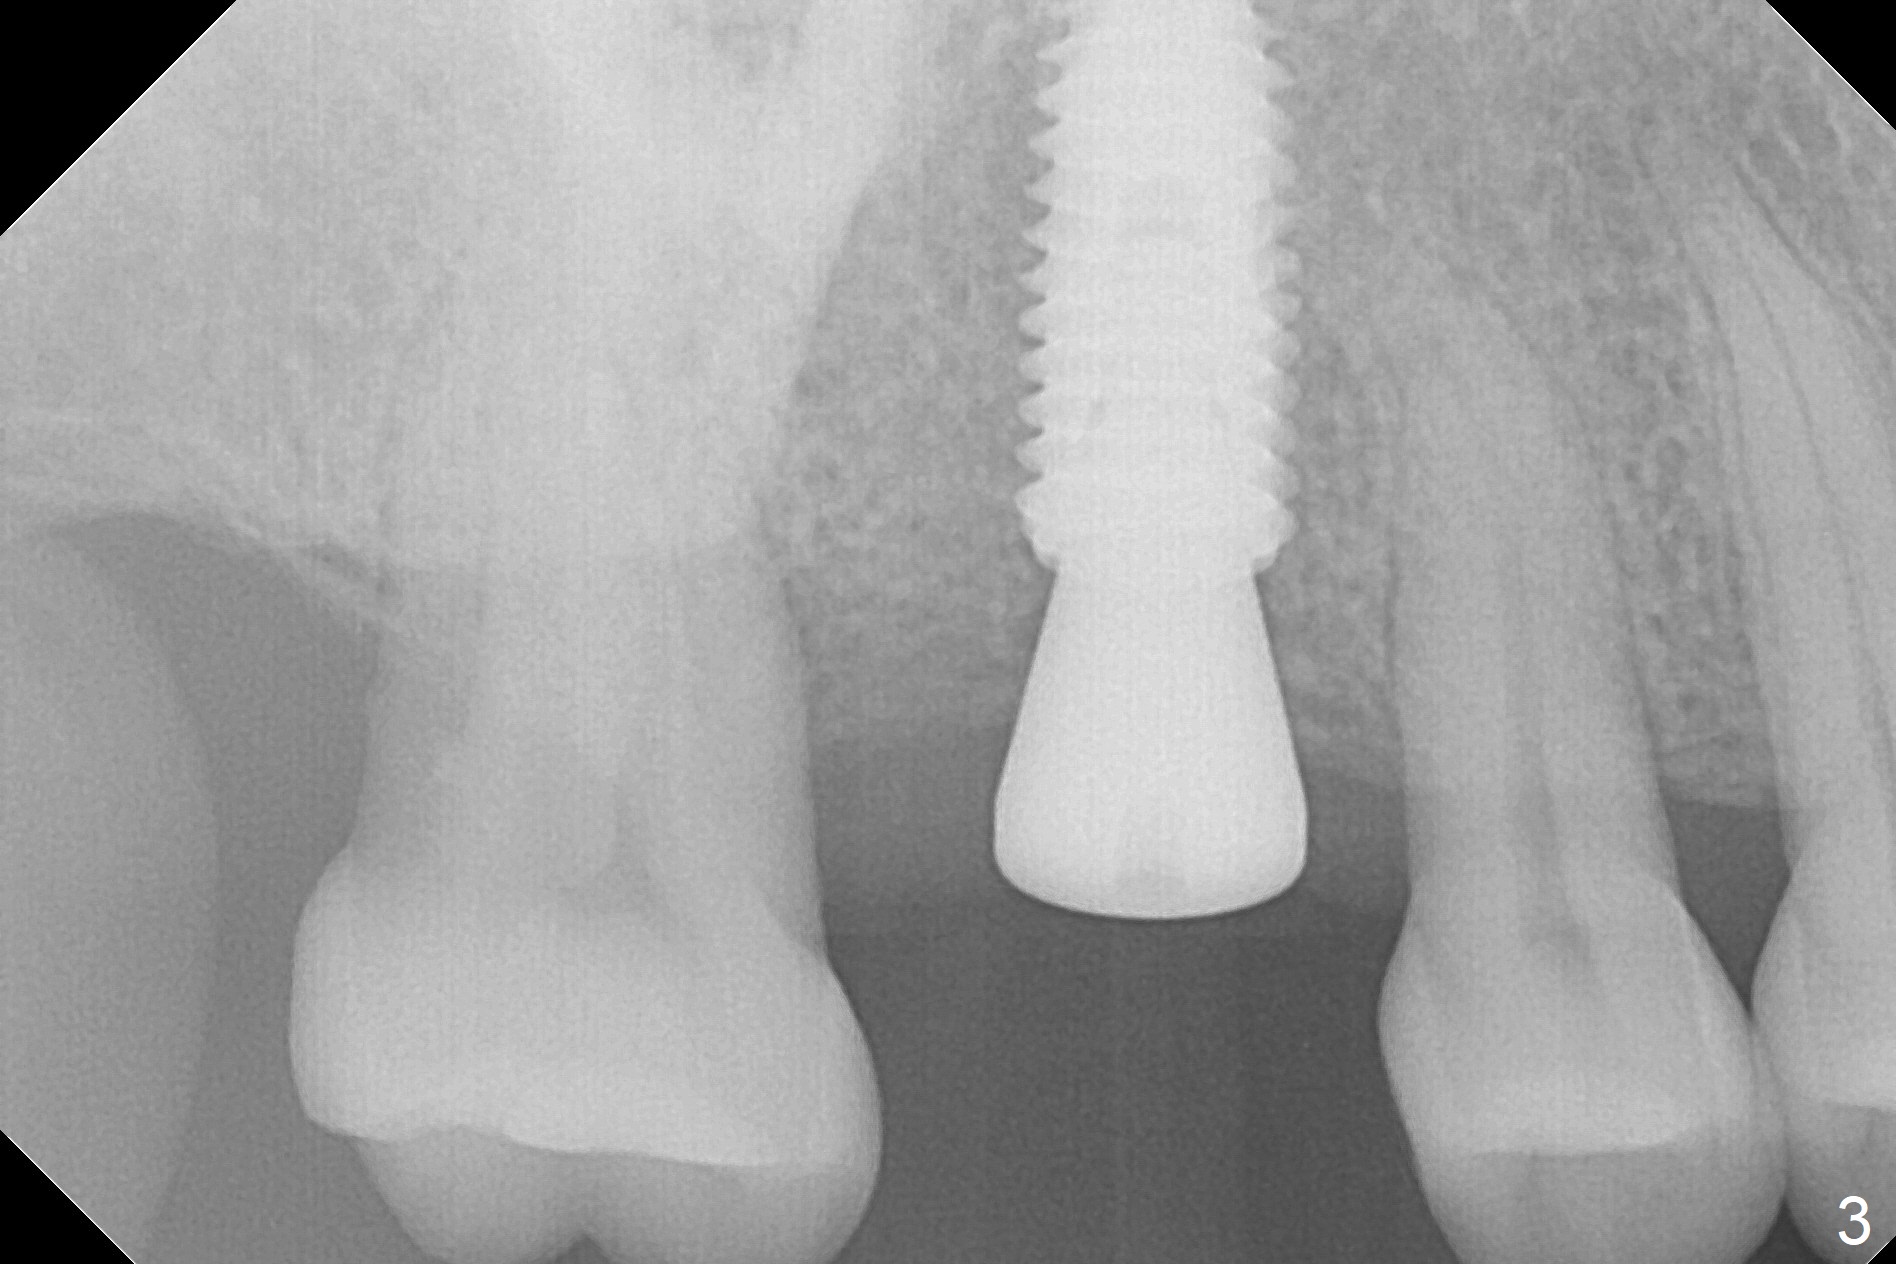

In order to place a 5x11.5 mm implant at #3 completely in depth, the preop CBCT coronal section is reanalyzed (Fig.1). It appears that extra 1 mm osteotomy does not perforate the sinus floor. After finishing osteotomy according to the guide plan, a 3.5x13 mm drill is used ~ .5 mm shy of the depth without sign of sinus membrane leakage. The implant is placed with apparently satisfactory depth, but it is quite close to the curved root tip of the neighboring tooth (Fig.2,3). In fact postop CBCT shows that there is a clearance (Fig.4). To prevent the similar event in the future, the implant should be designed slightly distal. The postop CBCT also shows that the extra depth is not necessary (Fig.4 *); it seems that the inherent 1.2 mm drill tip is sufficient for the depth overprep. The implant is stable for impression 6.5 months postop (Fig.5), whereas that placed immediately free hand is unstable 7.5 months postop. Two weeks later, the patient experiences severe pain when the abutment is being retightened. The crown at #3 is delivered 3 months later (9 months postop). It appears that the bone heals slow in this patient.